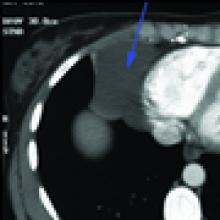

Patient is a 29 year old female, who was diagnosed with a pericardial cyst when she was 17 years old during a work-up of asthma. Recently, the patient presented with a persistent cough, and a repeat CT scan revealed increase in size of the cyst to approximately 6x6cm (Figures 1 and 2). Her past medical history was significant for Wolff-Parkinson-White syndrome. On examination no abnormalities were found. Since the cyst was enlarging, causing significant anxiety, and possibly contributing to her persistent cough, resection was recommended. Her cardiologists felt that her WPW Syndrome was not a contraindication to surgery.

| Figure 1. Preoperative Chest x-ray. | Figure 2. Chest CT scan showing right cardiophrenic pericardial cyst. |

Contrast CT scan has been the modality of choice to diagnose and to follow pericardial cysts[1,2]. However, no studies have been done to ascertain the superiority of contrast CT over MRI and echocardiography for diagnosis or for follow-up. On CT scan pericardial cysts are thin-walled, sharply defined, oval homogeneous masses . Their attenuation is slightly higher than water density – 30 to 40 HU[8]. They fail to enhance with intravenous contrast[8]. The frequency of follow-up imaging has not been established.